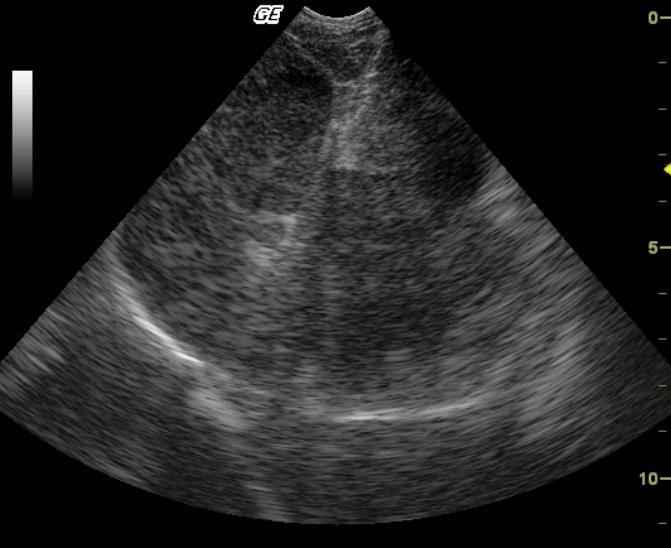

Coarse architecture is noted in both the spleen and liver with irregular capsular contour, echogenic and irregular tissue striations with nodular changes. This universal deviation from parenchymal architecture in both organs suggests a neoplastic process in both liver and spleen. The linear echogenic focus in the near field is a core biopsy needle.

Fibrosarcoma, liver and spleen